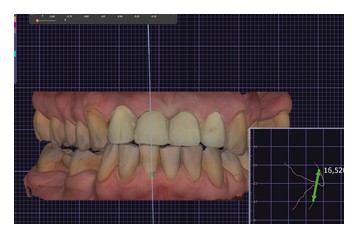

На этапе планирования комплексной реабилитации, было проведено интраоральное сканирование, фотопротокол, цифровая аксиография, данные которой использовались для последующей настройки виртуального артикулятора. Определено соотношение челюстей по нейромышечному протоколу с применением Миомонитора J5(TENS). По показаниям проведена репозиция нижней челюсти, в связи с чем была изготовлена каппа, фиксирующая терапевтическое исходное положение, так называемое Therapeutic Reference Position. То есть планирование имплантации проводилось уже не в исходном патологическом положении нижней челюсти, а в определенном терапевтическом, обеспечивая наиболее функционально выгодное расположение имплантатов относительно костного гребня. Позиционирование имплантатов на уровне 2.5, 2.6, 3.6, 4.6 - проводились под контролем хирургического шаблона.По завершению этапа остеоинтеграции и санации полости рта, приступили к этапу ортопедического лечения. В работе учитывались пожелания пациентки по эстетике. Объединив все полученные данные, мы приступили к построению зубных рядов с применением цифровых протоколов. В Программе Exocad был произведен расчет по индексу Шимбачи (LVI) ,что позволило определиться с оптимальной длиной фронтальной группы зубов, проведена моделировка Wax-up (Рис.8-9).

Рис. 8 Рис. 8

Рис. 9 Рис. 9